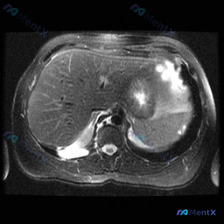

看到一个很有警示意义的影像病例,整理一下思路和大家分享: 最初的影像描述 这是一张腹部MRI轴位T2加权图像,可见一个边界清晰、形态规则的类圆形极高信号病灶,信号强度接近脑脊液(典型的“灯泡征”样表现),内部信号均匀,无明显分隔、结节或壁增厚,也未见对周围组织造成明显压迫或占位效应。 第一个容易踩的...

整理了一份脾脏占位的读片+分析思路,感觉这个病例的「混杂信号」挺有代表性,容易被带偏,分享出来一起理一理。 --- 一、先看影像核心表现 这份是上腹部MRI轴位T2加权像: - 肝脏、胃壁、腹膜后大血管这些都还好,没见明显异常; - 脾脏形态正常,但里面有一个类圆形占位,边界尚清; - 关键信号:T...